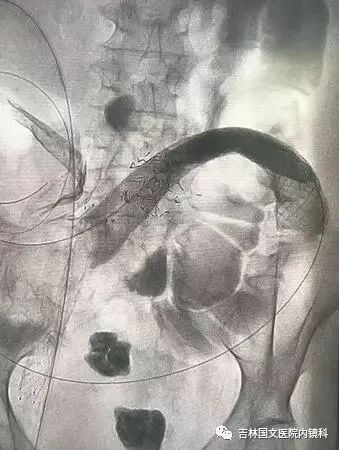

患者為結(jié)腸腫瘤致腸梗阻的病人,通過放置支架解除患者痛苦。手術(shù)開始,先置入導(dǎo)絲與導(dǎo)管,注入造影劑,顯示腸管走形,以確定狹窄段長度及部位,見乙狀結(jié)腸狹窄,造影劑可通過,但導(dǎo)絲至結(jié)腸狹窄處通過失敗,候主任決定聯(lián)合內(nèi)鏡,進行多學(xué)科合作。

邢主任迅速到達,循腔進鏡至乙狀結(jié)腸腫瘤處,見腫瘤環(huán)形生長,腫瘤似豆腐渣樣脆弱又霸道的侵占著本來就不寬敞的路,中指一樣粗細的腸鏡是無法通過了,只能做一盞指路的明燈,帶領(lǐng)導(dǎo)絲駛?cè)肽康牡?,在邢主任富有?jīng)驗的操作以及候主任隨機應(yīng)變地配合下,整個操作行云流水,導(dǎo)絲終于順利通過,送檢病理后,退出腸鏡。

又經(jīng)過一系列操作,腸道支架順利置入,患者術(shù)后排出大量稀便及氣體,腹脹明顯緩解,解決了患者的生理難題,提高了生活質(zhì)量。